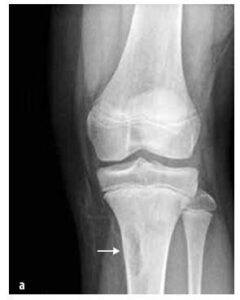

Оне се јављају чешће код деце него малигни тумори, нпр. тумори костију (остеоидни остеом, остеобластом, еозинофилни гранулом), тумори везивног ткива (фиброзна диплазија, неостеогени фиброма (види Слику 7)), коштане цисте, тумори хрскавице (хондроостеом, енхондром, хондробластома).

Слика бр. 7

Фиброма кости без остеогенезе